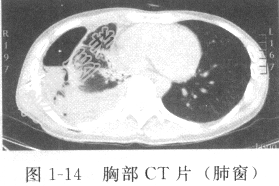

- [材料题] 患者男性,28岁,因“反复低热、盗汗2个月,咳嗽、咯血1个月”入院。入院胸部X线片发现右上肺空洞,右下肺胸腔积液。胸部CT平扫示右侧胸腔积液,右下肺炎症(图1-13、图1-14)。结核菌素(PPD)试验(++)。查体:营养中等,精神倦怠,体温38.2℃,右下肺呼吸音消失,叩诊呈浊音。既往有卡介苗接种史,否认结核患者接触史。